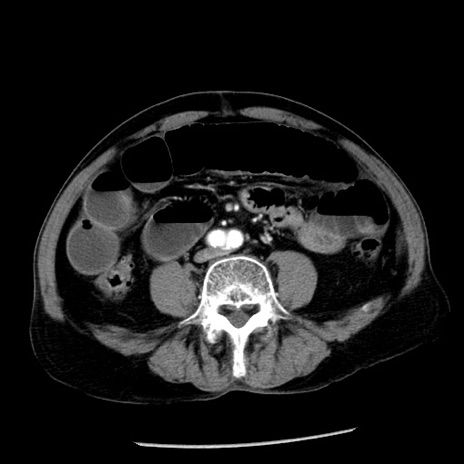

症例26(横断像)

【症例】80歳代男性

【主訴】嘔吐

【現病歴】昨晩2回嘔吐あり、今朝になっても嘔吐あり。来院。

【既往歴】胃潰瘍

【身体所見】意識清明、BT 37.6℃、BP 166/95mmHg、HR 100bpm、SpO2 97%、腹部:平坦・軟、腸蠕動音聴取良好、圧痛なし。

【データ】WBC 21900、CRP 1.46